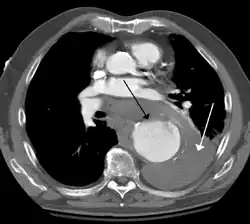

A thoracic aortic aneurysm is an aortic aneurysm that presents primarily in the thorax.

A thoracic aortic aneurysm is the "ballooning" of the upper aspect of the aorta, above the diaphragm. Untreated or unrecognized they can be fatal due to dissection or "popping" of the aneurysm leading to nearly instant death. Thoracic aneurysms are less common than an abdominal aortic aneurysm.[2] However, a syphilitic aneurysm is more likely to be a thoracic aortic aneurysm than an abdominal aortic aneurysm. This condition is commonly treated via a specialized multidisciplinary approach with both vascular surgeons and cardiac surgeons.

The principal causes of death due to thoracic aneurysmal disease are dissection and rupture. Once rupture occurs, the mortality rate is 50–80%. Most deaths in patients with Marfan syndrome are the result of aortic disease.